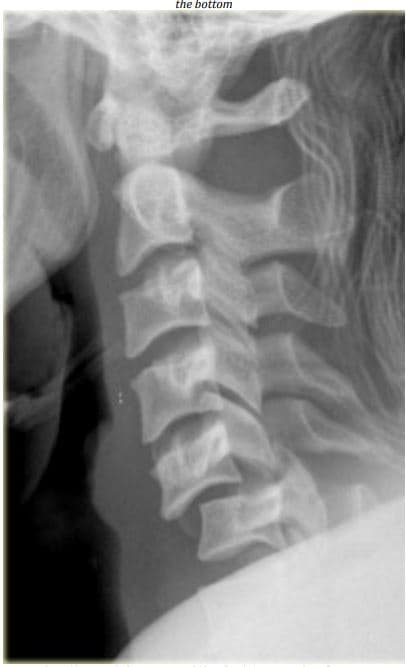

Look at the image. This is not a fracture. Describe the abnormality.

Name the section of the vertebral column shown.

Describe how the curvature of this section of the vertebral column is formed.